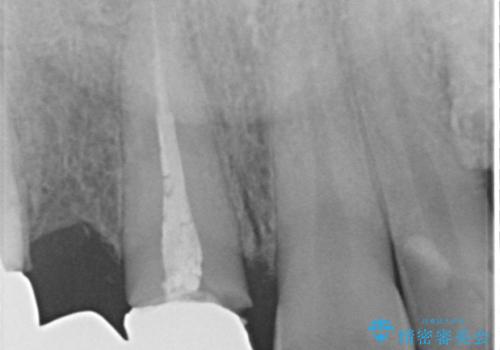

- 歯がない左側でものが咬めず、右側で咬むと歯が痛むので診て欲しいといらっしゃった方の症例です。

根尖病変が認められる歯は再根管治療を行い、歯根が破折していた左上4は抜歯しました。